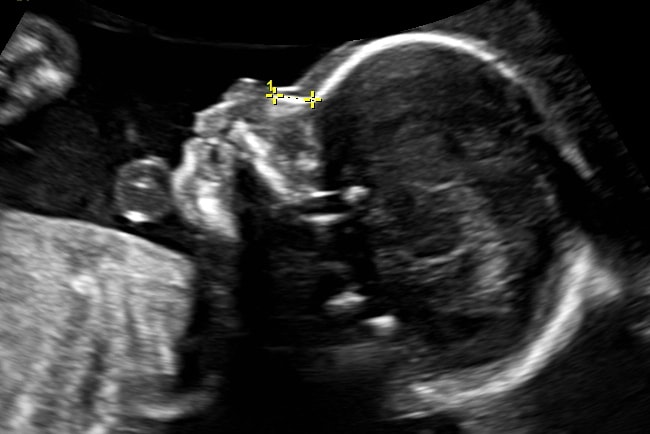

W artykule opublikowanym w Nature zespół opisuje udany eksperyment uzyskania w ten sposób pierwszych obrazów ultrasonograficznych u ludzi. Naukowcy zeskanowali przedramiona kilku ochotników i zaobserwowali wspólne cechy tkanek, takie jak mięśnie, tłuszcz i kości, mniej więcej na głębokość ok. 6 centymetrów. Obrazy te, porównywalne z konwencjonalnymi ultradźwiękami, zostały uzyskane zdalnie, z odległości ok. pół metra, za pomocą lasera skupionego na osobie ochotnika.

Jak przedstawiono w artykule, pełne bezkontaktowe ultradźwiękowe laserowe badanie ultrasonograficzne (LUS) – wykorzystujące źródła fotoakustyczne powierzchni skóry w połączeniu z laserowym wykrywaniem interferometrycznym – generuje cechy obrazu porównywalne z konwencjonalnym ultrasonografem i może rozwiązać konwencjonalne ograniczenia ultradźwięków.

Naukowcy przetestowali ten pomysł za pomocą zestawu lasera, używając zestawu laserów pulsacyjnych o mocy 1550 nanometrów do generowania fal dźwiękowych oraz drugiego lasera ciągłego, dostrojonego do tej samej długości fali, do wykrywania odbitych fal dźwiękowych. Drugi laser to czuły detektor ruchu, który mierzy wibracje na powierzchni skóry spowodowane przez fale dźwiękowe odbijające się od mięśni, tłuszczu i innych tkanek. Wibracje na powierzchni skóry, powodują zmianę częstotliwości odbierającego je lasera, które można zmierzyć. Dzięki czemu uzyskiwany jest obraz skanowanego fragmentu ciała.